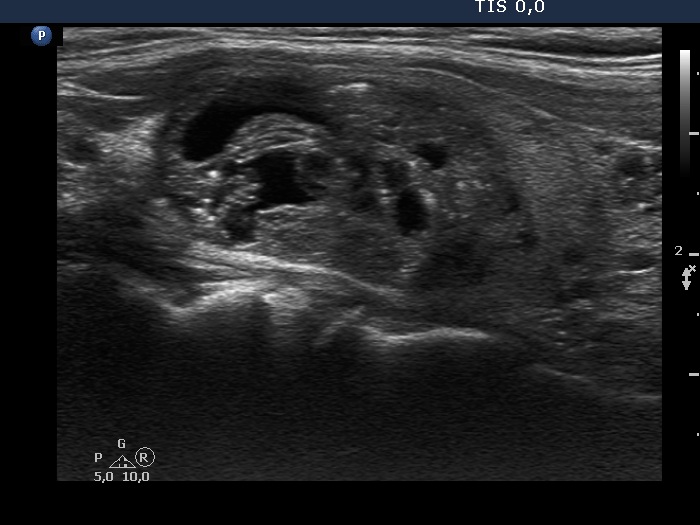

Benign cystic-colloid goiter (cytological diagnosis)

Besides various forms caused by posterior acoustic enhancement and a few unequivocal colloid crystals, there are non-specific pale granules and lines and several bright large amorphous figures in the ventral solid part of the nodule.